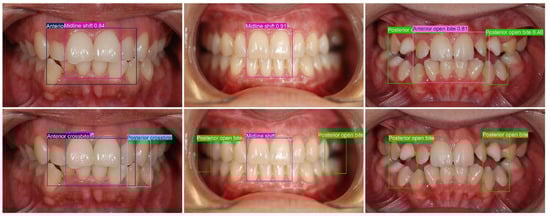

Multi-Class Malocclusion Detection on Standardized Intraoral Photographs Using YOLOv11

Background/Objectives: Accurate identification of dental malocclusions from routine clinical photographs can be time-consuming and subject to interobserver variability. A YOLOv11-based deep learning approach is presented and evaluated for automatic malocclusion detection on routine intraoral photographs, testing the hypothesis that training on a structured annotation protocol enables reliable detection of multiple clinically relevant malocclusions. Methods: An anonymized dataset of 5854 intraoral photographs (frontal occlusion; right/left buccal; maxillary/mandibular occlusal) was labeled according to standardized instructions derived from the Index of Orthodontic Treatment Need (IOTN) A total of 17 clinically relevant classes were annotated with bounding boxes. Due to an insufficient number of examples, two malocclusions (transposition and non-occlusion) were excluded from our quantitative analysis. A YOLOv11 model was trained with augmented data and evaluated on a held-out test set using mean average precision at IoU 0.5 (mAP50), macro precision (macro-P), and macro recall (macro-R). Results: Across 15 analyzed classes, the model achieved 87.8% mAP50, 76.9% macro-P, and 86.1% macro-R. The highest per-class AP50 was observed for Deep bite (98.8%), Diastema (97.9%), Angle Class II canine (97.5%), Anterior open bite (92.8%), Midline shift (91.8%), Angle Class II molar (91.1%), Spacing (91%), and Crowding (90.1%). Moderate performance included Anterior crossbite (88.3%), Angle Class III molar (87.4%), Head bite (82.7%), and Posterior open bite (80.2%). Lower values were seen for Angle Class III canine (76%), Posterior crossbite (75.6%), and Big overjet (75.3%). Precision–recall trends indicate earlier precision drop-off for posterior/transverse classes and comparatively more missed detections in Posterior crossbite, whereas Big overjet exhibited more false positives at the chosen threshold. Conclusion: A YOLOv11-based deep learning system can accurately detect several clinically salient malocclusions on routine intraoral photographs, supporting efficient screening and standardized documentation. Performance gaps align with limited examples and visualization constraints in posterior regions. Larger, multi-center datasets, protocol standardization, quantitative metrics, and multimodal inputs may further improve robustness. Full article